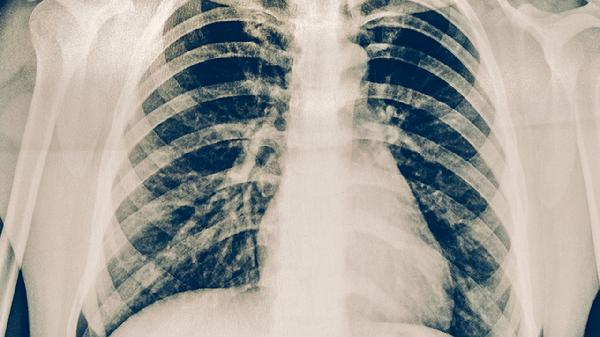

约半数患者出现局部软组织肿胀,触诊可及质地较硬的肿块。肿胀区域皮肤通常无发红,但可能伴有紧绷感。肿块大小不一,直径多在1-3厘米,由炎症导致的组织水肿和纤维增生形成。超声检查可见肋软骨增厚和周围软组织水肿。